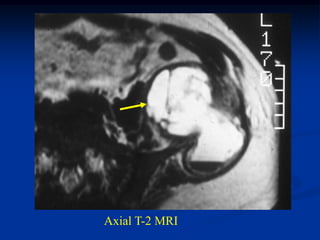

Case #1161             Endometrial CA

54 year female with endometrial CA uterus to pelvis

tumor

heterotopic ossification

One year later without treatment

osteoid

Photomic from pelvic metastatsis

photomic of endometrial adenocarcinoma